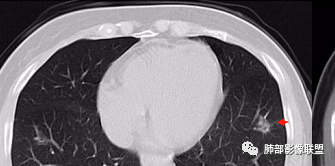

2、CT表现为两肺下叶结节影、斑片影、磨玻璃影,沿支气管血管束分布,部分支气管壁显示增厚。粗略一看部分病灶内似可见“细网格影”,但是仔细观察,可发现此“细网格影”不同于我们常见的“细网格影”,尤其是右肺下叶病灶,可以观察到病灶内部的网格上有高密度结节感或颗粒感,部分层面见“反晕征”,且反晕的边缘亦可观察到结节感。未见胸腔积液。

本例病变以两肺下叶为主,非结核好发部位,通常会想到感染性病变,右肺下叶病灶高密度结节感、反晕征,较为符合继发性肺结核(间质浸润为主),但双肺散落的相对柔和淡薄小片影给诊断带来困惑。